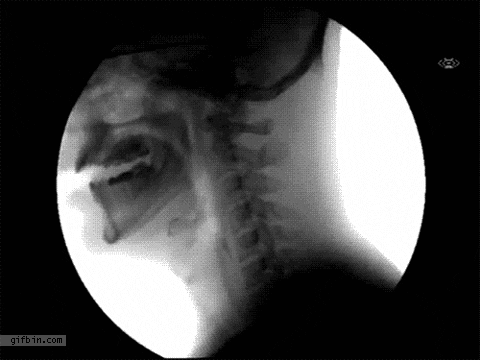

«Я проглотила ретейнеры в средней школе. Я проснулась посреди ночи с болью в груди и сказала родителям, но они не обратили внимания, потому что в то время я много кашляла. На следующий день мы никак не могли найти мои ретейнеры, а боль в груди всё не проходила. Мы решили сделать рентген, и угадайте, что мы на нём увидели?»